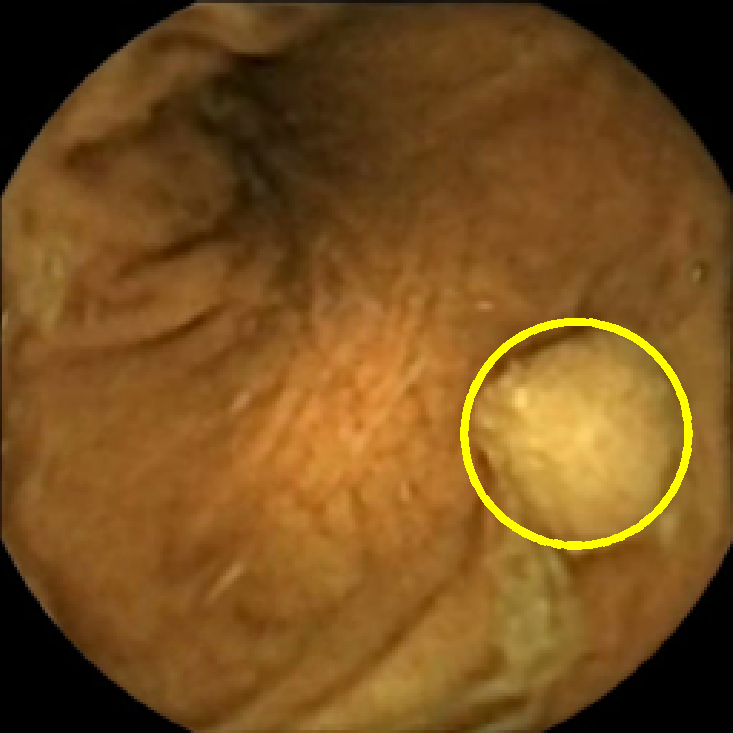

The examples of incorrect classification of frames are presented in Figure 6. The first two examples show false negatives, each highlighting a possible source of classification error. The example in column (a) shows the case where the feature corresponding to the polyp was too stretched out and thus was rejected by the eccentricity criterion (21). In contrast, the feature corresponding to the polyp in column (b) has passed the combined geometric criterion (22), but the radius was below the threshold of the binary classifier. Examples in columns (c) and (d) show the two sources of possible false positives. The false positive detection in column (c) is due to insufficient illumination correction. The bright spot is not fully corrected at the pre-processing stage and subsequently generates a polyp-like feature in the mid-pass filtered frame that happens to pass through all the criteria. Finally, in column (d) a mucosal fold is classified as polyp. Note that such cases are the most difficult to deal with, as the mucosal folds can often be hard to distinguish from polyps even for a human operator.